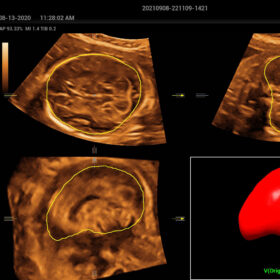

- Smart Scene 3D – Full Stack smartness obstetric solution empowered by ZST+. Comprehensive 3D/4D OB imaging solution with comprehensive fetal parts coverage.

One Key for favorite fetal part imaging, reducing manual adjustment - Smart Face – Automatic removal of occlussions over fetal face with one click

- Smart OB – Accurate auto measurements of most frequently examined parameters BPD/HC/FL/AC/OFD with a single click

- Smart FLC 2D/3D – Automatic Follicle Counting and measurements in 2D/3D mode